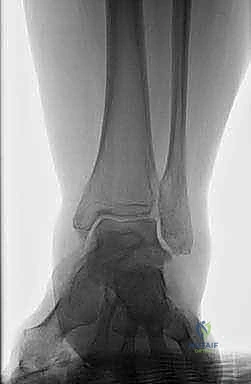

يتكون مفصل الكاحل الأساسي من التقاء عظمة قصبة الساق (Tibia) وعظمة الشظية (Fibula) مع عظمة الكاحل (Talus). وأسفل عظمة الكاحل تقع عظمة الكعب (Calcaneus)، حيث يشكلان معاً المفصل تحت الكاحل (Subtalar Joint) المسؤول عن الحركة الجانبية للقدم. عندما تتعرض هذه المنظومة الدقيقة لانهيار هيكلي، تتحول الحركة من فعل طبيعي إلى مصدر للألم المبرح والإعاقة.

يُعد مرض السكري غير المنتظم السبب الأول لتلف الأعصاب المحيطية. يفقد المريض الإحساس بالألم، مما يؤدي إلى استمرار المشي على كسور دقيقة في عظام القدم دون الشعور بها. والنتيجة هي انهيار كامل لقوس القدم وتفتت عظمة الكاحل (Talus).

3. استئصال العظام التالفة (Talectomy)

في حالات "شاركو" المتقدمة، تكون عظمة الكاحل (Talus) مجرد فتات عظمي ميت (Avascular Necrosis). يتم استئصال هذه العظمة بالكامل، بالإضافة إلى إزالة أي غضاريف متبقية من أسفل قصبة الساق وأعلى عظمة الكعب لضمان تلامس عظمي حيوي ونظيف.

4. تحضير قصبة الساق وعظمة الكعب

بعد إزالة العظام التالفة، يتم تسوية سطح عظمة قصبة الساق (Tibia) وعظمة الكعب (Calcaneus) بحيث يتطابقان تماماً. هذه الخطوة حاسمة لضمان استقامة القدم (Alignment) وتجنب أي قصر زائد في طول الطرف.